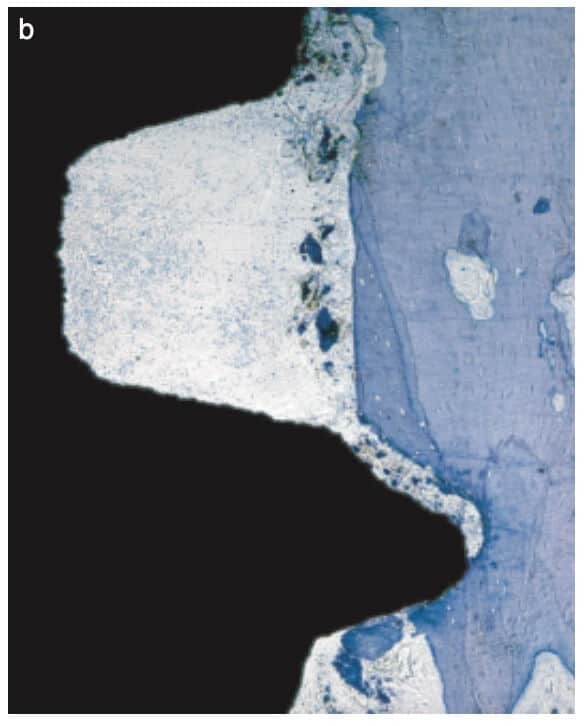

The “big deal” however was on the implant they used: It looked like Straumann, but it was not.

Not only it had very protruding threads, but there was an additional “pitch” at the top of each thread which would have probably made the traditional Straumann users of that time scream in disgust! So this implant never made it to humans, but remained in the notoriously small market of Beagle-dog implants. Nevertheless, this design was genius for the purpose of the experiment, as it created areas of compression (at the pitch of each thread) and areas of no contact, or empty chambers in the surface between two threads.

Right after implant placement, friction stability was achieved thanks to the pitches of the threads biting tight into the bone walls, while the non-contact areas filled with blood clot. The big news came however on the 4th day, when an interesting pattern of bone resorption occurred at the coronal side of the pitch! Why resorption? Obviously the compression of the bone there had killed a zone of bone about 50 μm, which was now being cleared away.

To get the whole picture, we need to look closer at the other side of the coin and see what happens in the no-contact areas. There, at 1 week one could see another exciting development: contact osteogenesis! New mineralized bone was created on the surface of the implant in the empty chamber, where previously only blood clot existed. This was something hardly seen on the smooth surface implants, but was apparent in the SLA implants introducing another factor in the equation, the implant surface.

The collective message of these amazing experiments was the while bone is being cleared at the pitch of the thread, new bone is getting created on the implant surface at the no-contact areas! Surface is a significant factor here, with contact osteogenesis being well established at 2 weeks in humans with SLAactive implants, as documented by another great study by Lang et al (4). Lang as well, noted absence of new bone at the pitch of the thread after 1 week, but significant new bone in non-contact areas, where the “jumping” distance between the implant and the bone was short. Again, this message seen somewhat superficially, lead many to believe that the lower and fewer the implant threads, the better the implant would be, reinforcing the anecdotal concept of “aggressive” and “passive” implants. But as you can’t judge a book by its cover, you shouldn’t also judge an implant by its threads! The missing part here was that an implant with few and shallow threads will be unlikely to offer adequate primary stability!